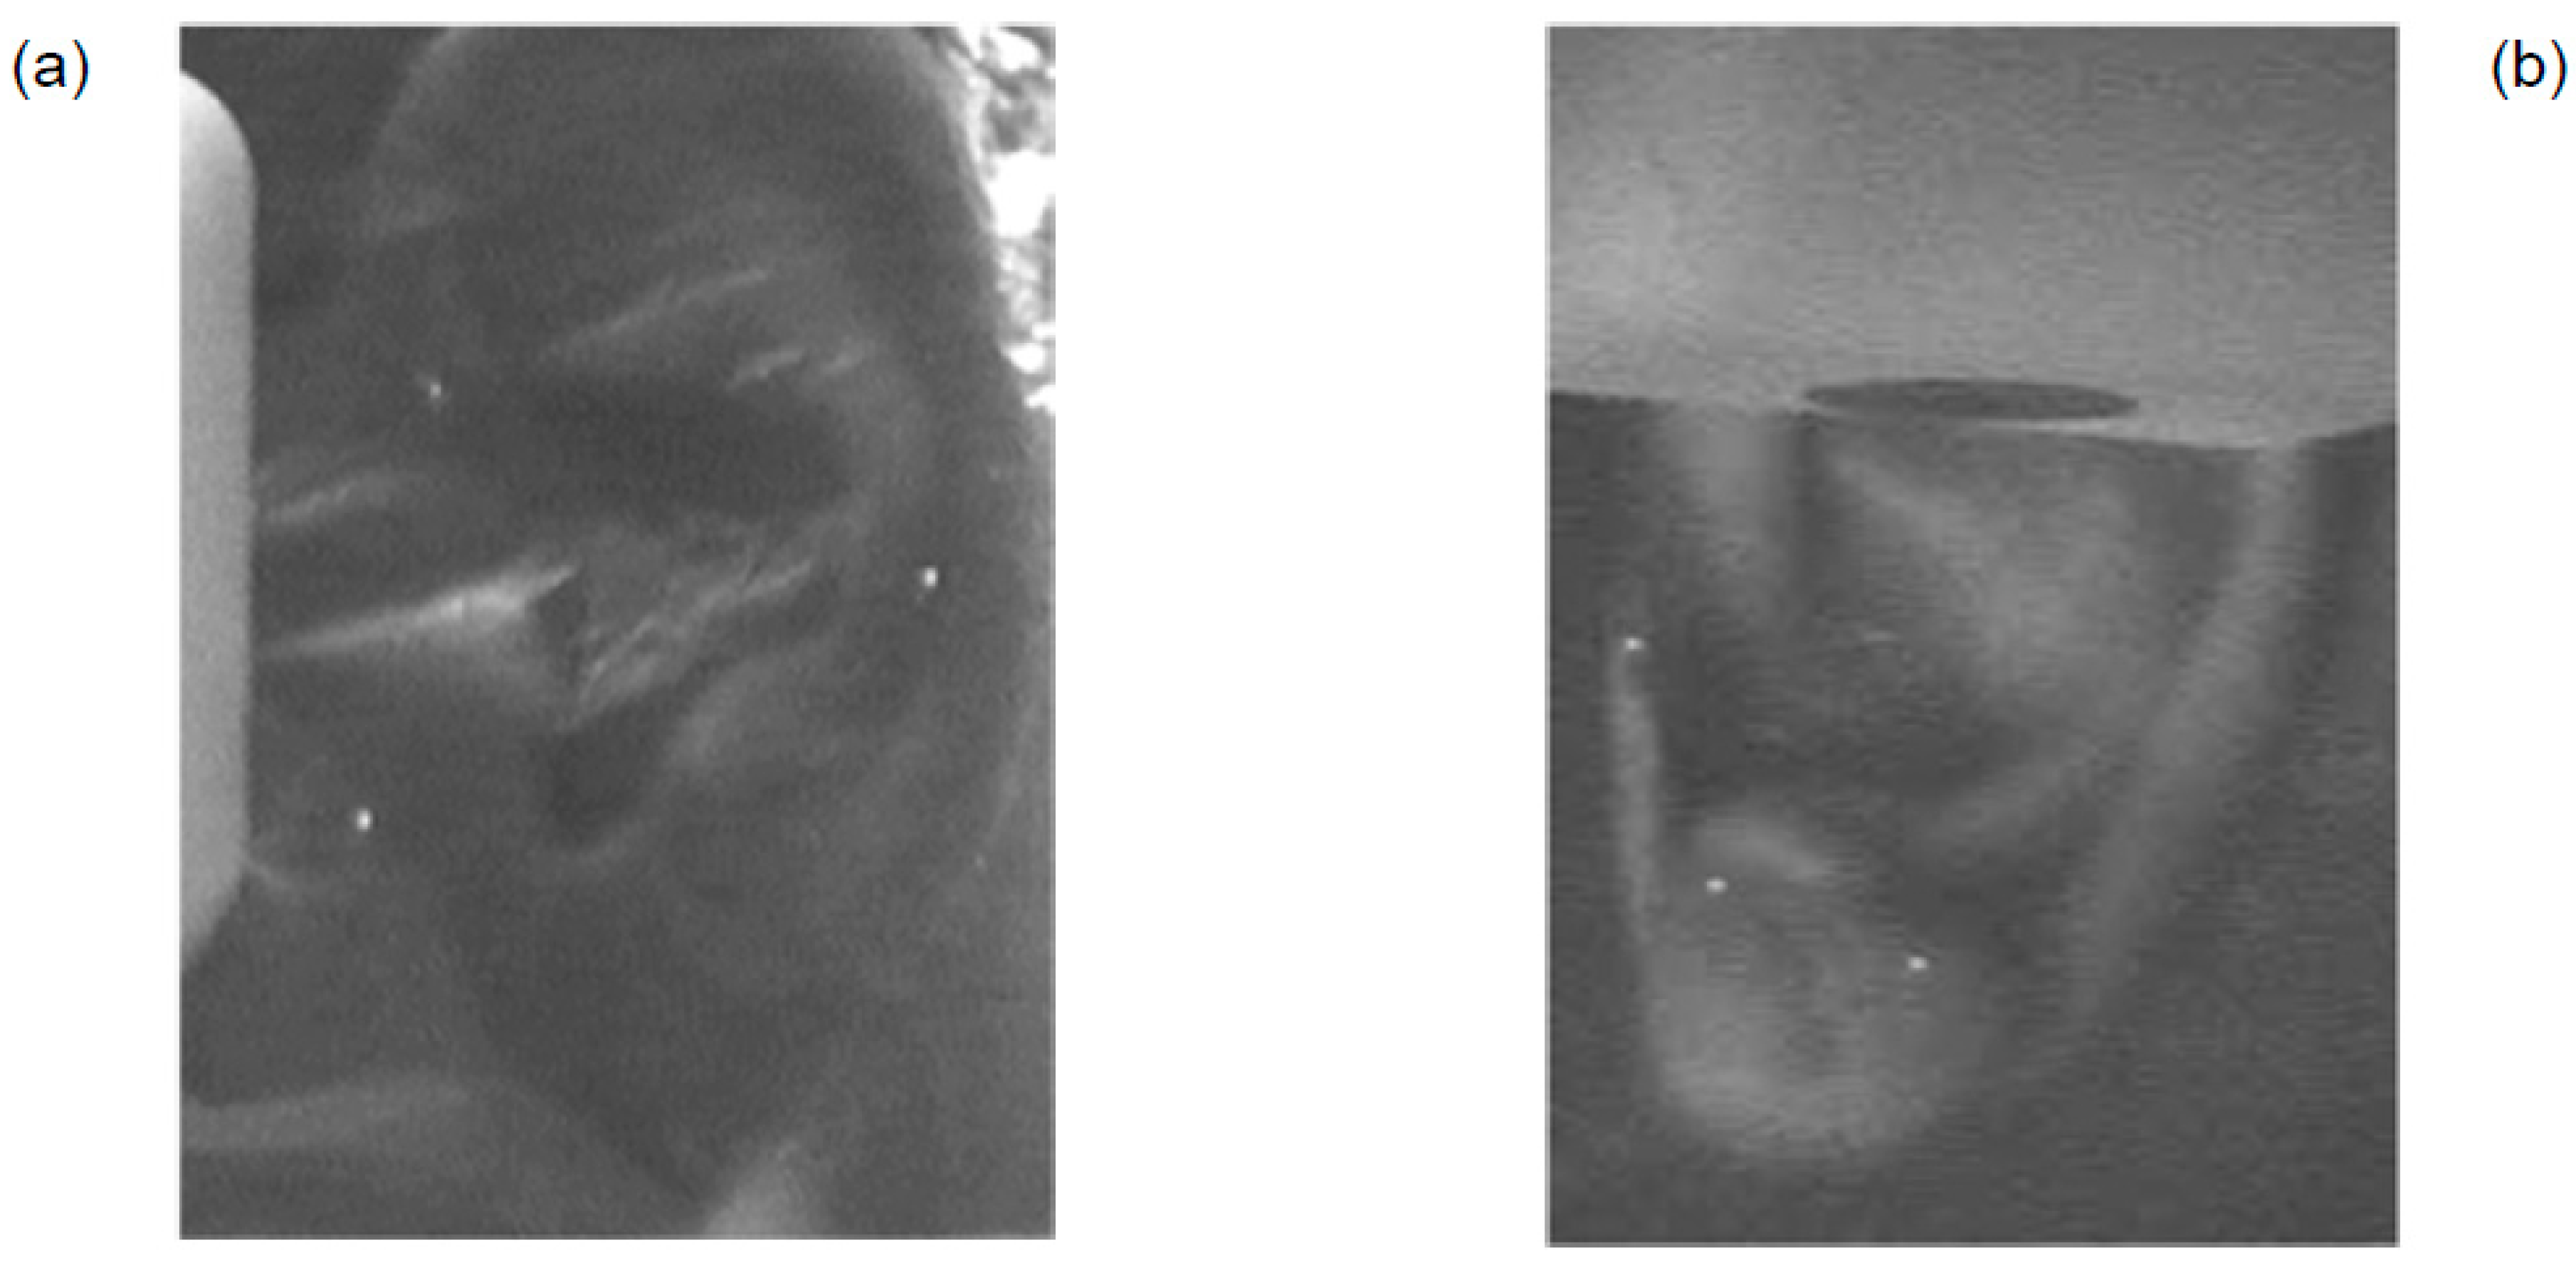

The following publications were from the French scientist P. de Vernejoul et al. [267,268,269,270]. Technetium-99m [99mTc] in the form of sodium pertechnate was administered subcutaneously to a depth of 3-5 mm to a group of patients and healthy volunteers, volume of 0.05 ml containing a single dose of 10 MBq. Introduction of the RAI into the point K-7 (Fu Liu) located on the inside surface of the leg led to linear migration of the isotope to 30 cm from the injection site (Figure 6b). A local diffusion in different directions was observed (Figure 6a) when it was introduced outside the point.

When RAI was introduced into point St-43 (Xian Gu), located on the dorsum of the foot, the isotope migrated in proximal and distal directions along the tendon-muscular channel of the Stomach [267]. When RAI was administered in GB-36 (Wai Qiu) point located on the outer surface of the tibia and point St-41 (Jie Xi), located on the borderline between the foot and shin, a linear migration of the isotope in the distal and proximal directions was observed. When RAI was administered to a point LI-18 (Fu Tu) in the center of the sternocleidomastoid muscle, the isotope migration was observed toward the upper lip on the opposite side, i.e., alongside the Large Intestine channel [268].